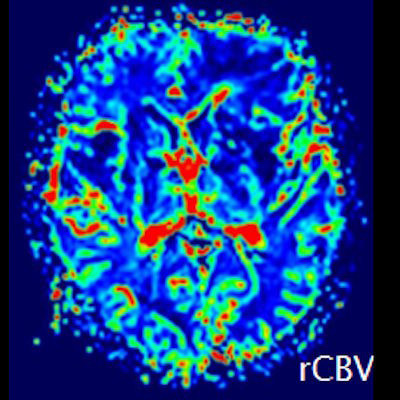

- (C) Difüzyon ağırlıklı görüntülerde sol frontaldeki kitle lezyonunda difüzyon kısıtlama bulgusu (oklar) mevcut olup perfüzyon MRG’de rCBV haritasında belirgin perfüzyon artışı izlenmemektedir (ok).

- Perfüzyon MRG’de düşük-orta düzey CBV değerleri izlenir. Lenfomalarda düşük CBV değerleri, kötü prognoz göstergesidir.